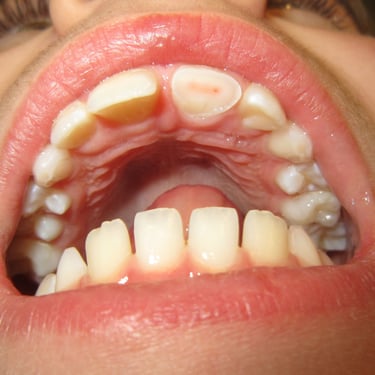

Reabsorción Externa

La reabsorción externa es la pérdida de tejido dental desde el exterior del diente hacia adentro, a menudo como resultado de un trauma o infección.

Los pacientes pueden no tener síntomas hasta que el diente se afloje.

El tratamiento incluye la eliminación de la causa y, a veces, un tratamiento de conducto. En casos severos, puede ser necesario extraer el diente.